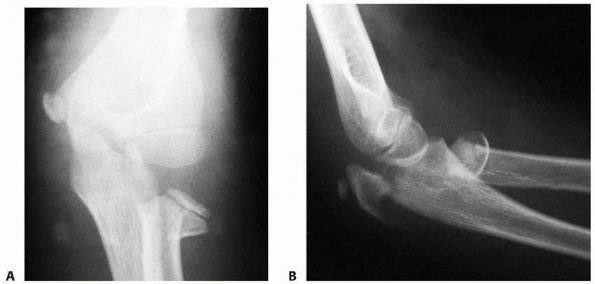

FIGURE 11-11 Valgus (type B) injury. A.

Three weeks after the initial injury, there was evidence of distal migration of this Salter-Harris type IV fracture fragment. Periosteal new bone formation has already developed along the distal metaphyseal fragment (arrow). B. Six months after the initial injury, there is evidence of an osseous bridge formation between the metaphysis and the epiphysis. Subsequently, the patient had secondary degenerative arthritis with loss of elbow motion and forearm rotation. |